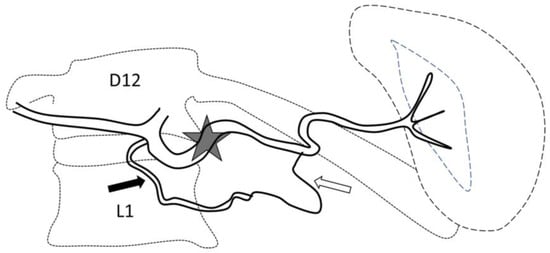

Figure 4.

Secondary pseudoaneurysm formation 6 days after preventive proximal splenic artery embolization (PPSAE). (A) shows PPSAE with a vascular plug (star) and the development of collateral circulation (arrows) alongside pseudoaneurysm formation (curved arrow). (B) displays the dominant collateral circulation via the gastroepiploic artery (striped arrows). (C) Microcatheter selection of the gastroepiploic artery for distal embolization (blank arrows).